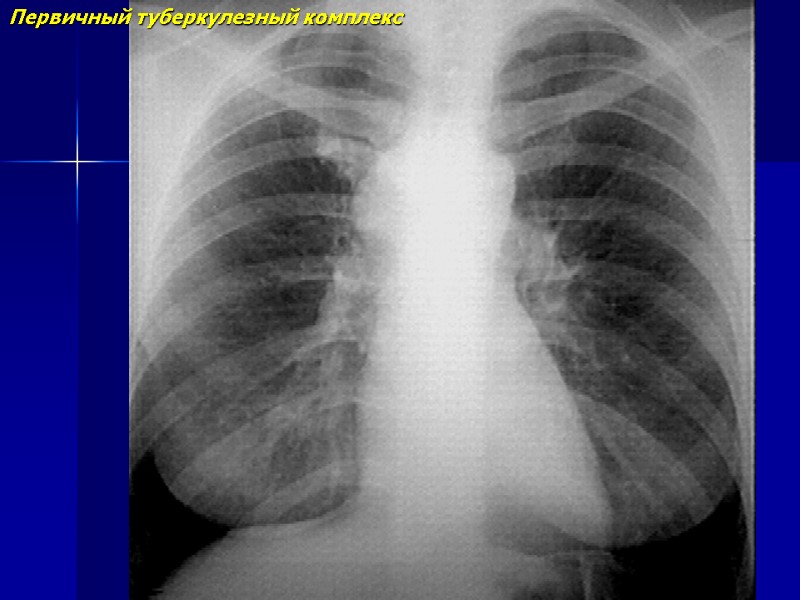

Первичный туберкулезный комплекс